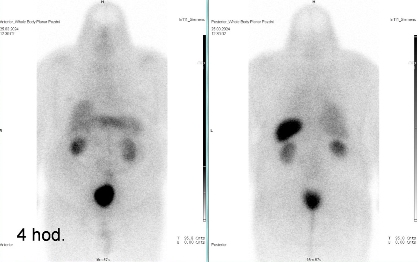

Scintigrafie Octreoscanem:

I. v. jsme aplikovali 190 MBq analogu somatostatinu značeného 111In

(přípravek OctreoScan firmy Curium Netherlands B. V.) a provedli pomocí hybridní tomografické scintilační kamery Symbia Intevo firmy Siemens opatřené kolimátory pro střední energie planární celotělovou scintigrafii a cílenou tomografickou scintigrafii (SPECT) břicha a pánve kombinovanou s CT za 4 a 24 hod.

(obr. 1-2).

/ Obr. č. 1: Celotělová scintigrafie v přední a zadní projekci 4 a 24 hod. po aplikaci OctreoScanu.